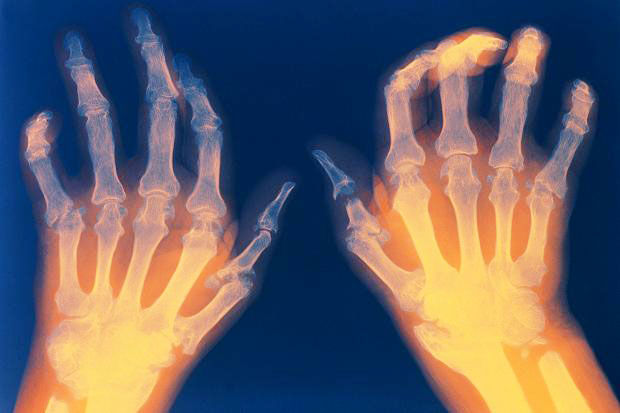

I стадия. На этом этапе распознать болезнь крайне сложно. Симптомы почти полностью отсутствуют. За исключением некоторой отечности вокруг суставов пальцев конечностей. Вовремя проведенные диагностические мероприятия выявляют истончение костей, поражение средних суставов и изменения мышечной ткани.

II стадия. На костной ткани, окружающей суставы, формируются эрозии. Мышцы начинают атрофироваться, появляются ревматоидные узелки. Суставы отекают и увеличиваются в размерах.

III стадия. Анатомическая конструкция суставов полностью деформируется. Двигательная функция нарушается. Утолщаются мягкие ткани. Конечности приобретают специфическую форму (в частности, кисти рук отклоняются в сторону).

IV стадия. Поражения становятся многочисленными, осуществлять движение невозможно. В процесс втягиваются внутренние органы. Больше всего страдают печень и почки. Нарушается сердечно-сосудистая деятельность, на коже появляется характерная желтизна, отказывает селезёнка. Больной прикован к постели.

- Характерные «ревматоидные» симптомы: межфаланговые суставы неподвижны, завернуты вверх или вниз, отклонены в сторону;

- Пальцы утолщаются в ногтевой пластине и в местах сгиба;

- Деформация стопы, вследствие чего появляется дугообразное искривление голеней.